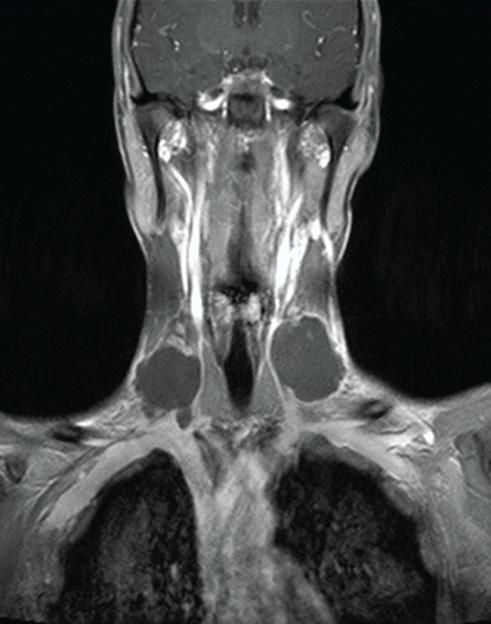

An MRI showed three large lumps around the ulcer, each measuring up to 5cm.

The patient also had two blood clots in his jugular vein.